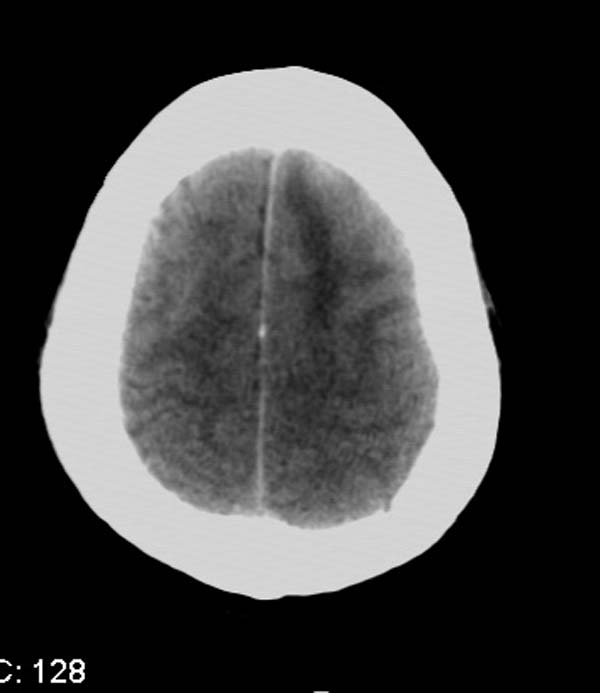

以下是引用拾荒者在2007-10-5 19:31:00的发言:[br]左额叶镰旁不规则形高密度影,中间见钙化灶及略低密度影,占位征象明显,周围有低密度水肿带环绕,首先考虑脑膜瘤。